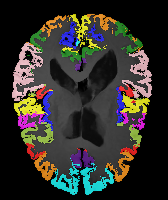

Brain MRI experiment: We also evaluate our method on the MindBooggle101 [4] brain MRIs with 32 cortical regions. We fuse corresponding segmentation labels of the left and right brain hemispheres. MindBoogle101 consists of images from multiple datasets, e.g., OASIS-TRT-20, MMRR-21 and HLN-12. After removing images with incorrect labels, we obtain a total of 85 images. We use 5 images from OASIS-TRT-20 as validation set and 15 as test set. We use the remaining 65 images for training. Manual segmentations in the N=1 and N=21 experiments are only from the MMRR-21 subset; this simulates a common practical use case, where we only have few manual segmentations for one dataset and additional unlabeled images from other datasets, but desire to process a different, new dataset. All images are 1mm isotropic, affinely-aligned, histogram-matched, and cropped to size . We apply sagittal flipping for training data augmentation. We use the same loss weights as for the knee MRI experiment except for , since cross-subject brain registrations require large deformations and hence less regularization.

Results: All trained networks are evaluated using Dice overlap scores between predictions and the manual segmentations for the segmentation network, or between the warped moving segmentations and the target segmentations for the registration network. Tabs. 1 and 2 show results for the knee and brain MRI experiments respectively in Dice scores (%). Fig. 2 shows examples of knee MRI registrations and brain MRI segmentations.

Brain results: Dice scores for segmentation and registration increase by about 2.6 and 3.5 respectively for the cortical structures of the brain MRIs.

Qualitative results: DA achieves more anatomically consistent registrations than the mono-networks on the knee (Fig. 2) and Brain MRI samples (see supplementary material).